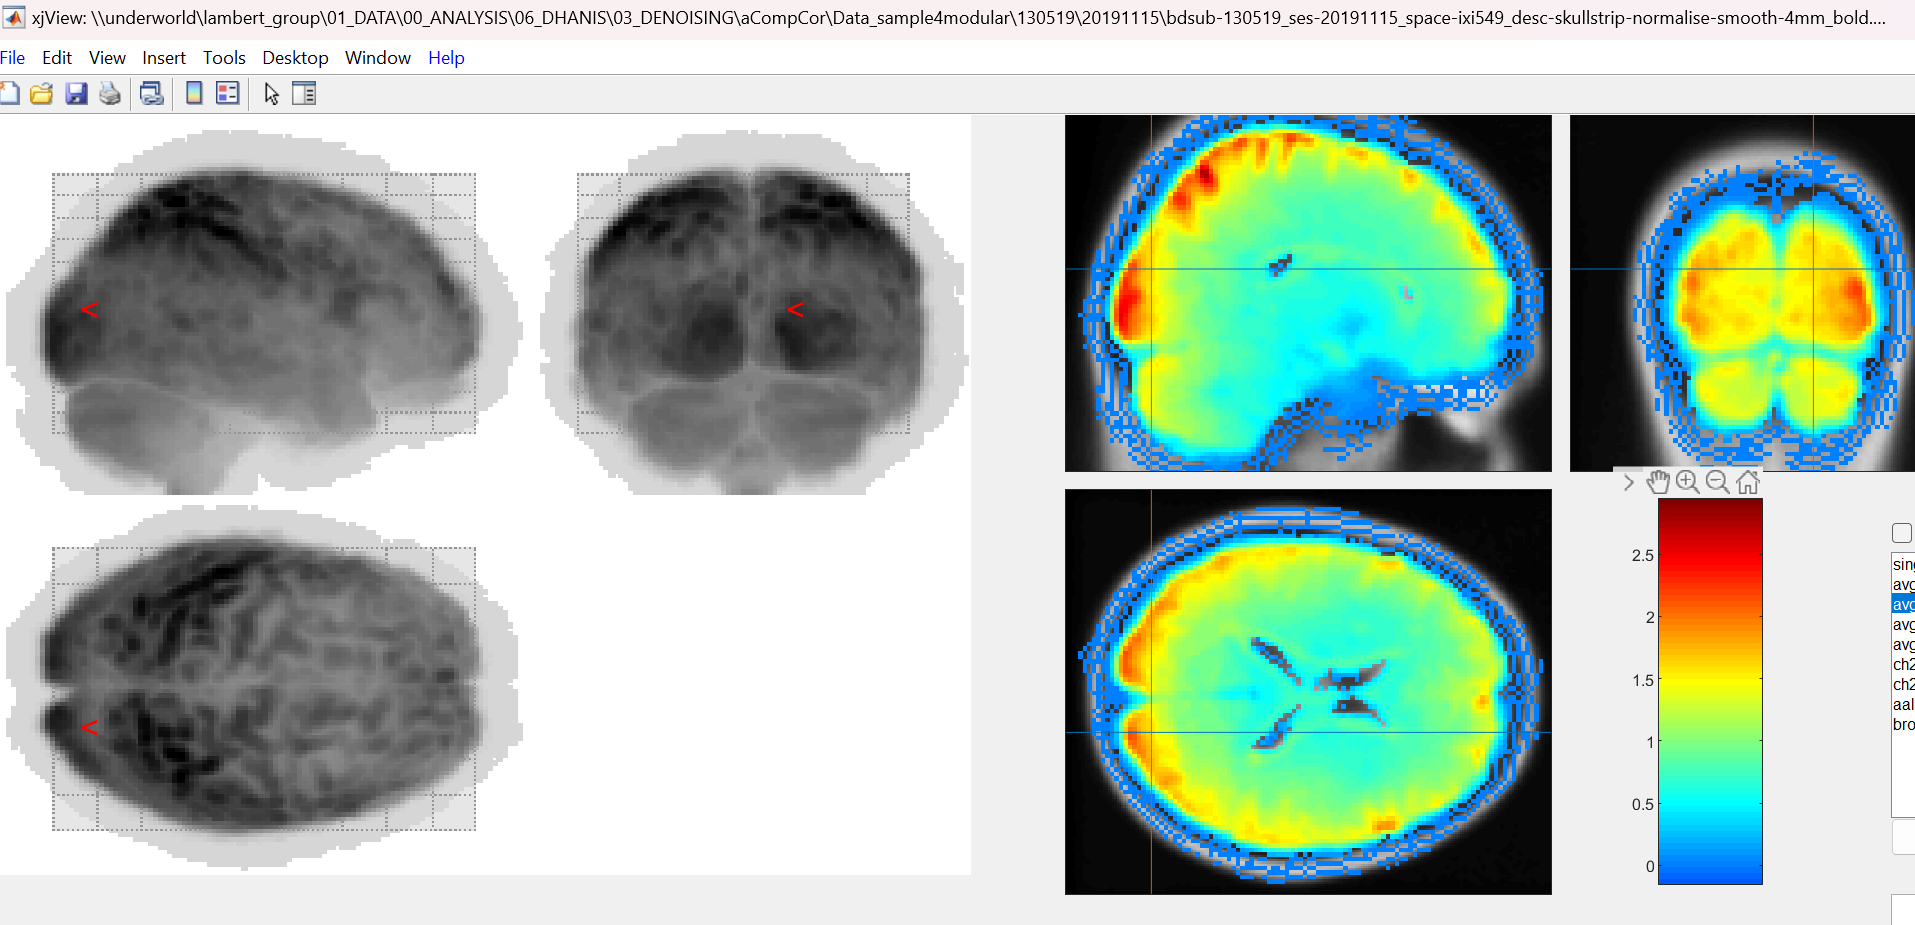

I do get the this aura around the images in both denoised (regression) and bandpass filter images. I don't get this in the GUI but I am guessing this is because there is no explicit masking suing the module. Just thought I would check that quickly.